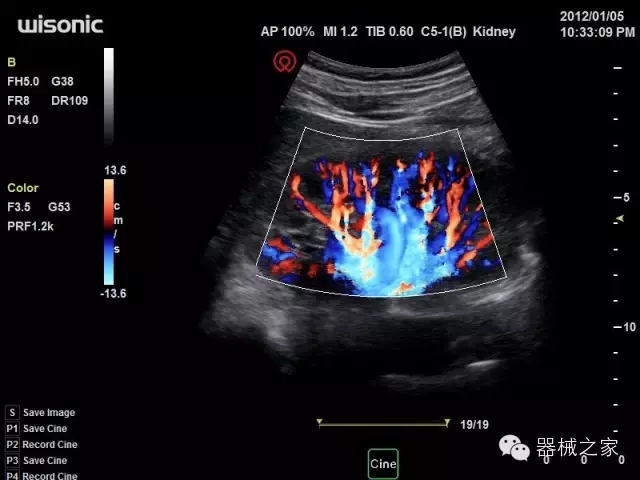

臨床圖片賞析

產(chǎn)品特點(diǎn)

·全球目前唯一一款配備主機(jī)雙探頭接口,整機(jī)重量(含電池)在5公斤以內(nèi)的便攜式彩超;

·一款互聯(lián)網(wǎng)彩超,只要有手機(jī)信號的地方就可以非常方便地實(shí)現(xiàn)遠(yuǎn)程會(huì)診和病案調(diào)??;

·鎂鋁合金外殼,堅(jiān)固可靠耐用;

·獨(dú)有的HoloTM PW 實(shí)時(shí)3取樣門PW成像技術(shù),精確進(jìn)行血管診斷;

·一鍵優(yōu)化B、Color、PW,Auto Doppler自動(dòng)識別血管位置、偏轉(zhuǎn)角度等,提高工作效率;

·30°超廣角精細(xì)偏轉(zhuǎn)成像技術(shù),更優(yōu)異的頻譜圖像;

·W+智能搜索引擎,快速尋找圖像;

·SSD、USB3.0保障開機(jī)快,導(dǎo)出圖像更快,減少等待時(shí)間;

·WIFI、網(wǎng)口、3G,多重聯(lián)網(wǎng)方式,全天候保障云端備份,不再擔(dān)心圖像丟失;

CFDA注冊證編號

·粵械注準(zhǔn)201522231208